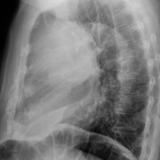

Case 9 Thymoma Lat

Date: 04/04/2010

Views: 3179